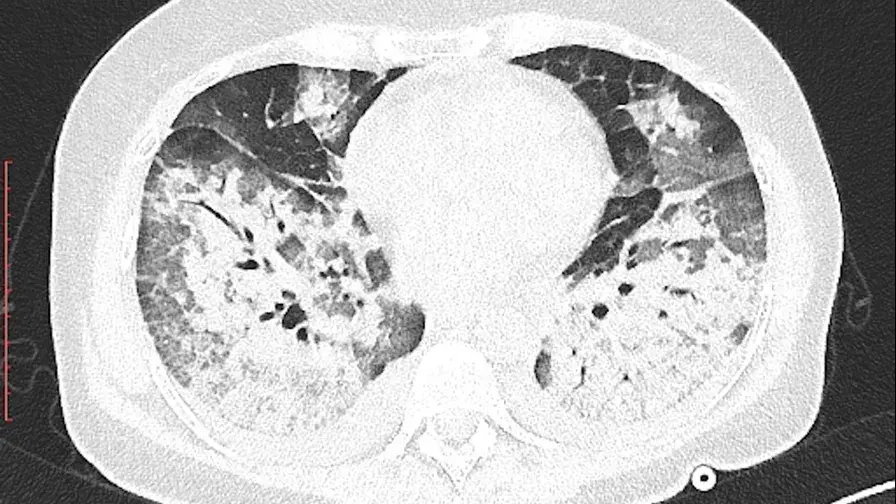

GE Healthcare, Orange Healthcare et TheraPanacea collaborent avec l’AP-HP et la Société d’Imagerie Thoracique pour créer une base de données inédite sur le COVID-19 et développer de nouveaux outils fondés sur l’intelligence artificielle. Un projet de recherche clinique sur le Coronavirus s’appuie sur l’annotation massive de 10 000 scanners thoraciques réalisés pour suspicion de COVID-19. Les données recueillies permettront de constituer une base de données sans précédent afin d’enrichir nos connaissances sur cette maladie, et d’évaluer l’apport de l’intelligence artificielle dans le diagnostic et l’évaluation du pronostic. L’expertise acquise pourra être mise à profit pour la prise en charge d’autres maladies pulmonaires.

• Cette collaboration vise à soutenir le projet STOIC (Scanner ThOracique pour le dIagnostic de la pneumonie liée au Covid-19) porté par le Professeur Marie-Pierre Revel, cheffe de l’unité d’imagerie cardiothoracique de l’hôpital Cochin, une étude d’envergure qui vise à analyser 10 000 scanners thoraciques effectués pour suspicion de COVID-19.

L’ensemble des données, provenant de nombreux hôpitaux publics parisiens, mais également de Rennes, Lyon et Strasbourg, constituera une base de données sans précédent sur le COVID-19.